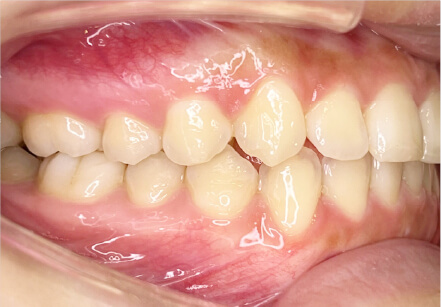

叢生の症例

9歳

女性

相談内容

マイオスマイルからの移行

カウンセリング・診断結果

上11捻転、上33スペース不足、インビザで歯列矯正

治療内容・方法

全額アライナー矯正 クリアコレクト

術後の経過・現在の様子

リンガルアーチ使用

治療のリスク

痛み・歯根吸収・歯肉退縮・虫歯・後戻り

費用・治療期間

(マウスピース矯正のみ)440,000円+220,000円 月々27,500円、9ヶ月+myo1年10ヶ